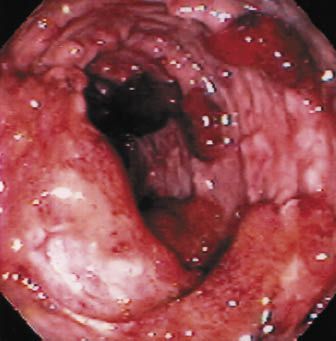

Stool examination, sigmoidoscopy or colonoscopy, and biopsy are indicated to confirm the presence of colitis and to rule out infectious causes in patients who have bloody diarrhea, rectal urgency, or tenesmus. Order microbiological studies for bacteria, parasites, and amebas; include assays for Escherichia coli 0157:H7 and Clostridium difficile, particularly in patients who have recently been hospitalized or treated with antibiotics. Characteristic endoscopic and histological findings in the absence of evidence of an infectious cause suggest ulcerative colitis. The mucosal changes characteristic of ulcerative colitis, as detected by proctosigmoidoscopy or colonoscopy, include loss of the typical vascular pattern, granularity, friability, and ulceration (Figure).

Figure – Pseudopolyps (distinct, irregular raised areas of normal-appearing mucosa) are seen here among areas of friability, fibrous stranding, and ulceration in a 29-year-old man with ulcerative colitis. These growths, which represent a combination of reactive hyperplasia and mucosal ulceration, are not an uncommon finding in patients with severe or chronic ulcerative colitis. (Courtesy of Chad M. Sisk, DO.)